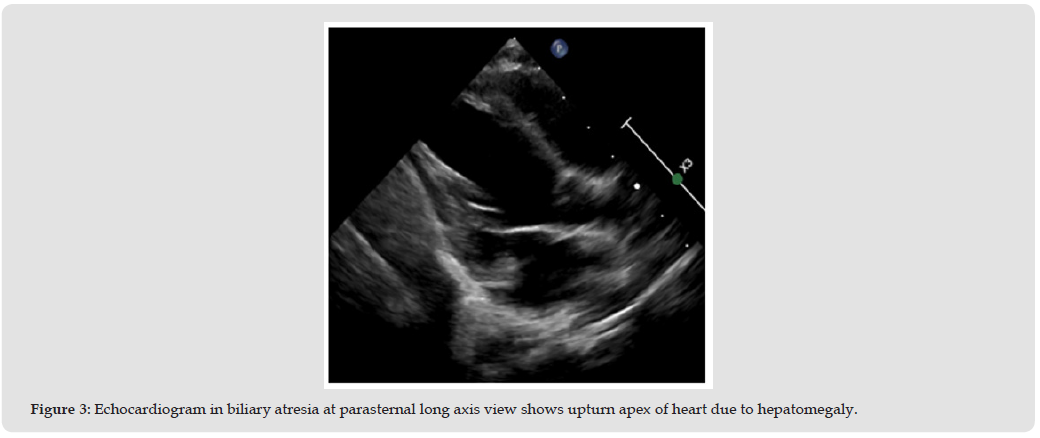

But the better property of echocardiography consist of inexpensively, non-invasively, portability and radiation safety, promote echocardiography popular equipment of imaging [4]. The Alagille syndrome and biliary atresia or liver cirrhotic most often cause patients to have liver enlargement [5] This condition is an obstacle to echocardiography in the parasternal area because it will cause the apex to be raised, resulting in difficult images adjust. This condition is also a limitation of examination in the subcostal view, Because the liver is enlarge and the tissue changes, it has a hard appearance, making it impossible to apply pressure to produce a clear image. [6] (Figure 3) The angiogram was used in case of need evaluated pulmonary hypertension and the role of intervention. (Figure 4).